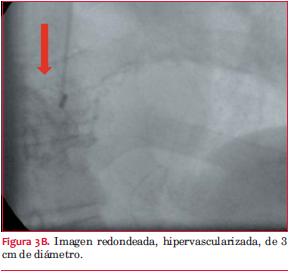

Cineangiocoronariografía: sin lesiones obstructivas significativas. Origen anómalo de arteria circunfleja en seno de Valsalva derecho. De la circunfleja nace grueso vaso de neoformación con imagen redondeada hipervascularizada de 3 cm en sector posterior (figuras 3 A y B).